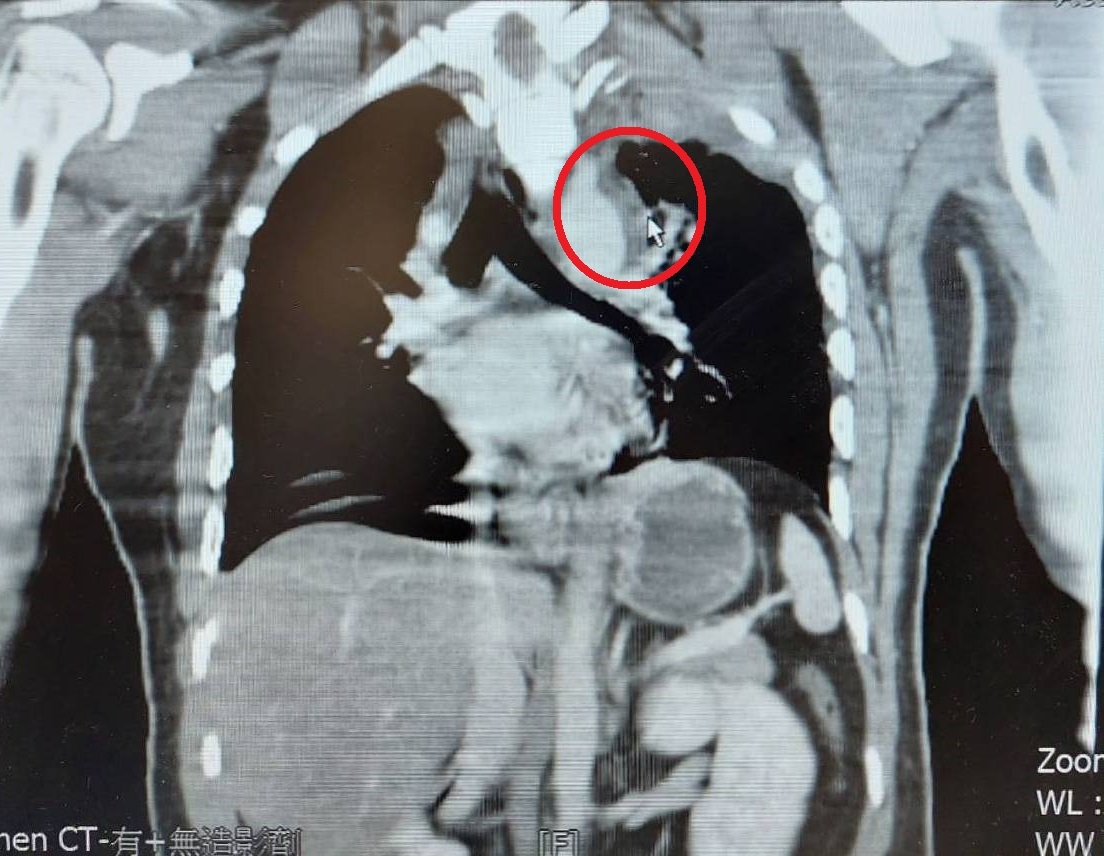

胸腔因速度急速變化,造成撞擊拉扯,導致發生外傷性胸主動脈剝離(紅圈箭頭處)。

大千綜合醫院心臟外科醫師陳嘉葦表示,外傷性胸主動脈剝離是因為在加速的過程中,突然快速的減速,導致胸腔經猛烈撞擊、壓迫,並和大動脈相連的韌帶拉扯,而造成主動脈損傷。其嚴重程度可分為四級:內膜裂傷、血腫、假性動脈瘤、及最嚴重的大動脈破裂,由於傷者常合併多處器官損傷出血,所以若為第三、四級程度,建議要立即手術治療,第一、二級則可視病人當下狀況,決定是否保守治療或手術。